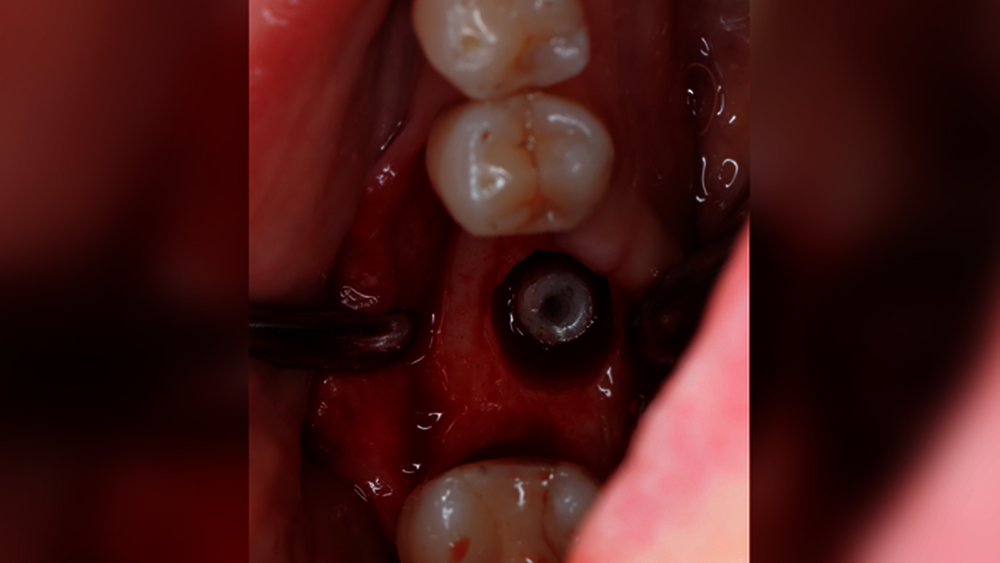

Wenn wir über technische Komplikationen in der Implantologie nachdenken, dann fallen uns sicher zuerst Dinge wie Keramikabplatzungen der Suprakonstruktion, Schraubenlockerungen, Gerüstfrakturen oder Retentionsverluste ein. Schraubenbrüche und Abutmentbrüche gehören Gott sei Dank nicht zu unserem Alltag, genauso wenig wie die schlimmste technische Komplikation: der Bruch des osseointegrierten Implantats (Abbildungen 1 und 2). Sicher kennen die meisten Kolleginnen und Kollegen aus ihren Praxen frakturierte Implantate als eher seltene Ereignisse – die jedoch meist einen sehr großen Behandlungsaufwand nach sich ziehen. Aber wie viele Implantate brechen wirklich beziehungsweise wie hoch ist das Risiko für eine Implantatfraktur?